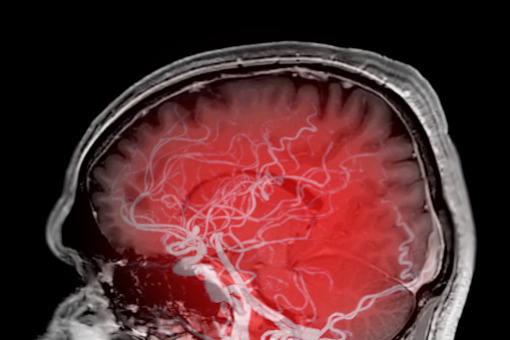

Nieleczone tętniaki mózgu zwiększają ryzyko chorób psychicznych

Nieleczony niepęknięty tętniak wewnątrzczaszkowy (UIA) wiązał się z o 10 procent wyższym ryzykiem chorób psychicznych, szczególnie wśród osób młodszych – wykazało nowe badanie.